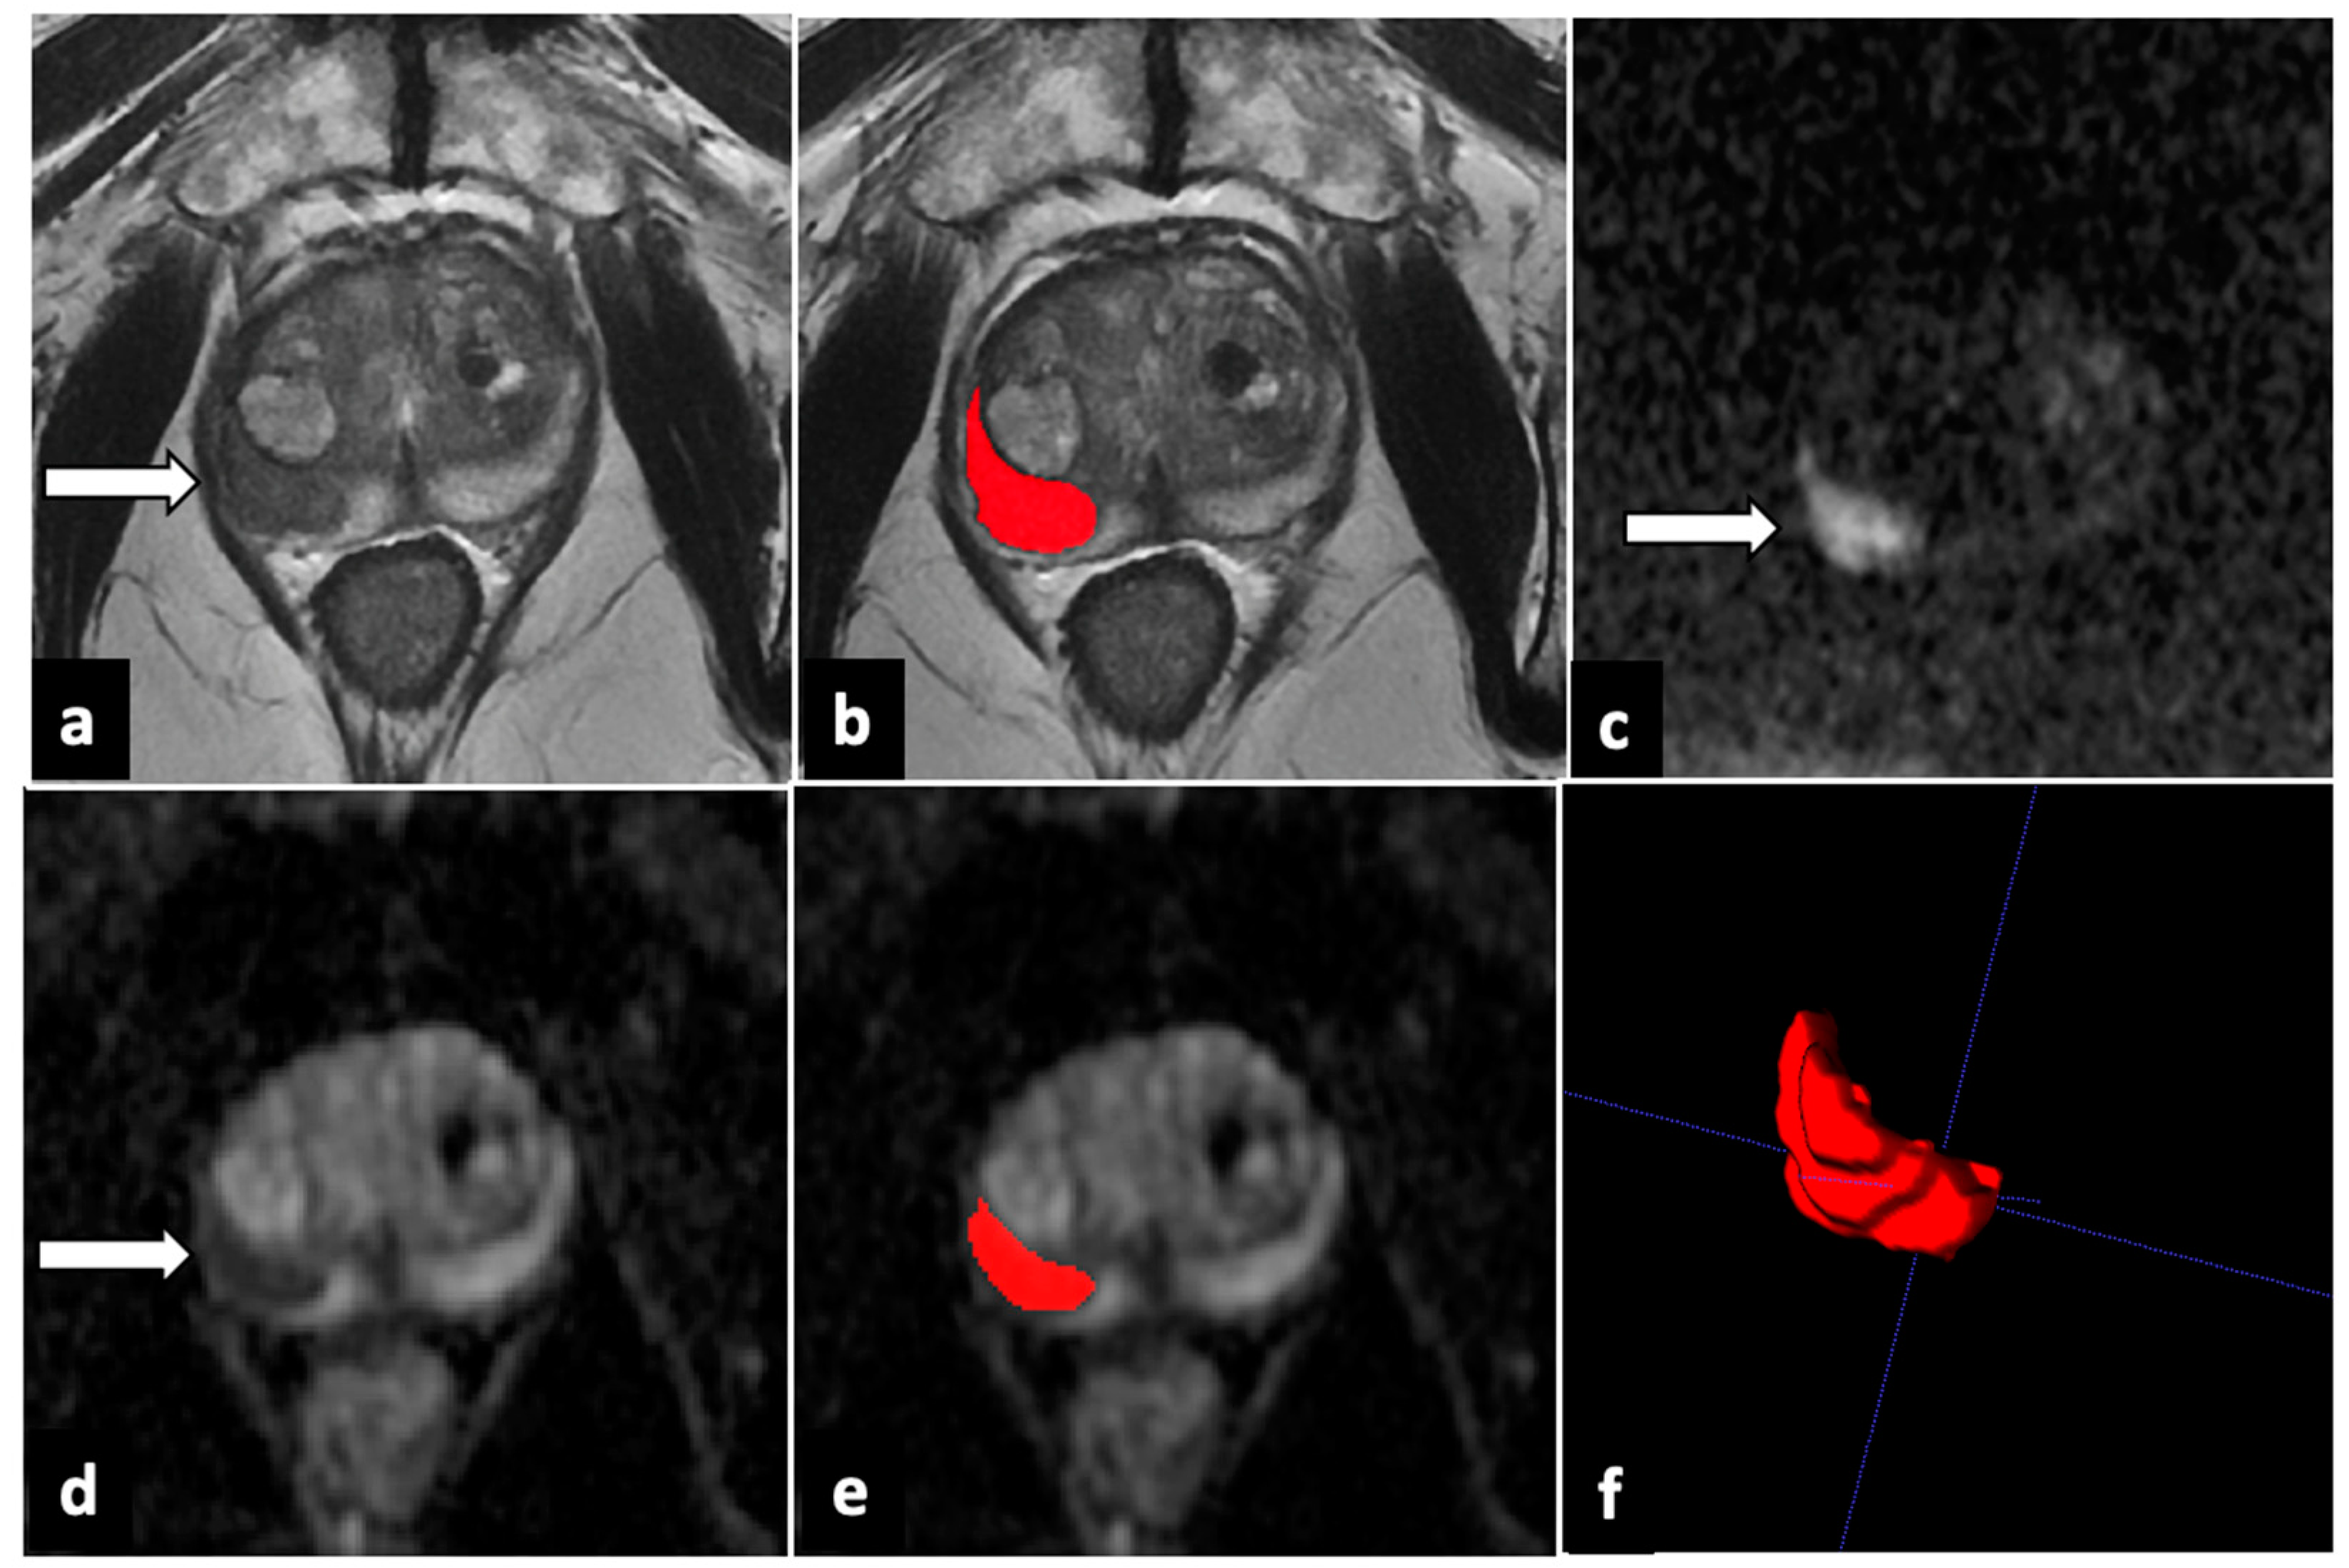

2.4. Image Analysis and Lesion Segmentation